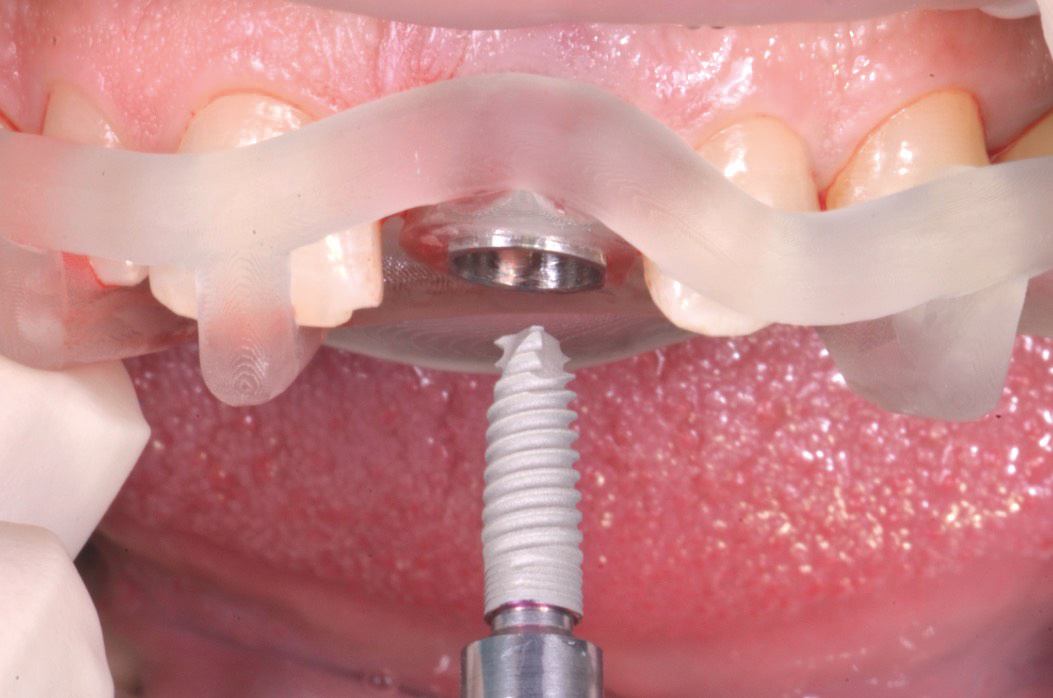

Una volta posizionata la dima chirurgica si è eseguita l’osteotomia guidata con frese a diametro crescente ed è stato posizionato l’impianto (MIS V3, MIS Implants ltd global, Bar Lev, Israele)(fig.7,8).